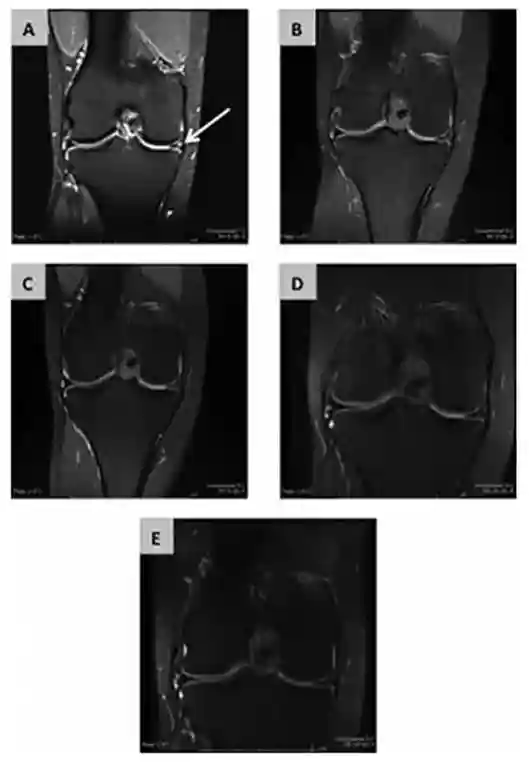

研究人员对55例部分关节切除患者进行关节腔内注射MSCs的研究,实验组患者注射同种异体MSCs,对照组患者注射透明质酸钠。通过VAS及self-Lysholm评估后得出结论,损伤症状得到缓解,1年MRI的追踪检测证实经过MSCs治疗的患者半月板体积显著增加。

图解(在六个月的评估中,半月板体积增加已超过15%)

(图b术后3个月;图c术后6个月;图d术后12个月;图e术后24个月)